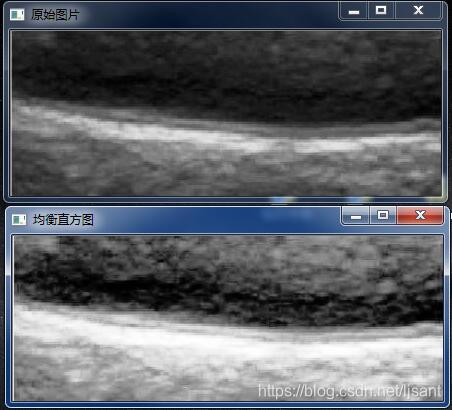

2)灰度均衡(直方图均衡)

在1)的情况下,开始用均衡的手法。我的理解所谓灰度均衡:是为了转换后的直方图是平的,满足每一个灰度级上有相同像素点的输出图像,但是实际过程中不会出现类似一条平的直方图,因为像素点最多只有256,太少。经过一些列的计算公式

void HistB(cv::Mat &image){int table[256] = { 0 };int nr = image.rows;int nc =image.cols*image.channels();for(int j =0;j<nr;j++){uchar * data =image.ptr<uchar>(j);for(int i=0;i<nc;i++){table [data[i] ]++;}}unsigned char bmap[256];for (int i = 0; i < 256; i++) {long temp = 0;for (int j =0;j<= i;j++){temp+=table[j];}bmap[i] =(unsigned char)(temp*255/image.rows/image.cols);//均衡化,这个公式是经过计算推导得来的}for(int j =0;j<nr;j++){uchar * data =image.ptr<uchar>(j);for(int i=0;i<nc;i++){data[i] = bmap[ data[i]];}}imshow("均衡直方图", image);

}